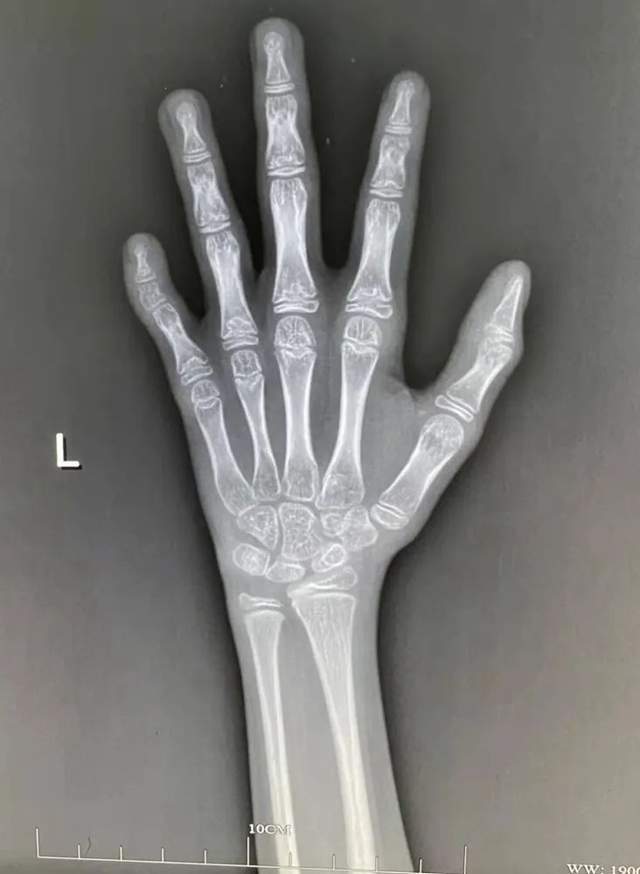

请各位专家看骨龄

跪请那位医生帮看看孩子骨龄的片子可以吗?感谢